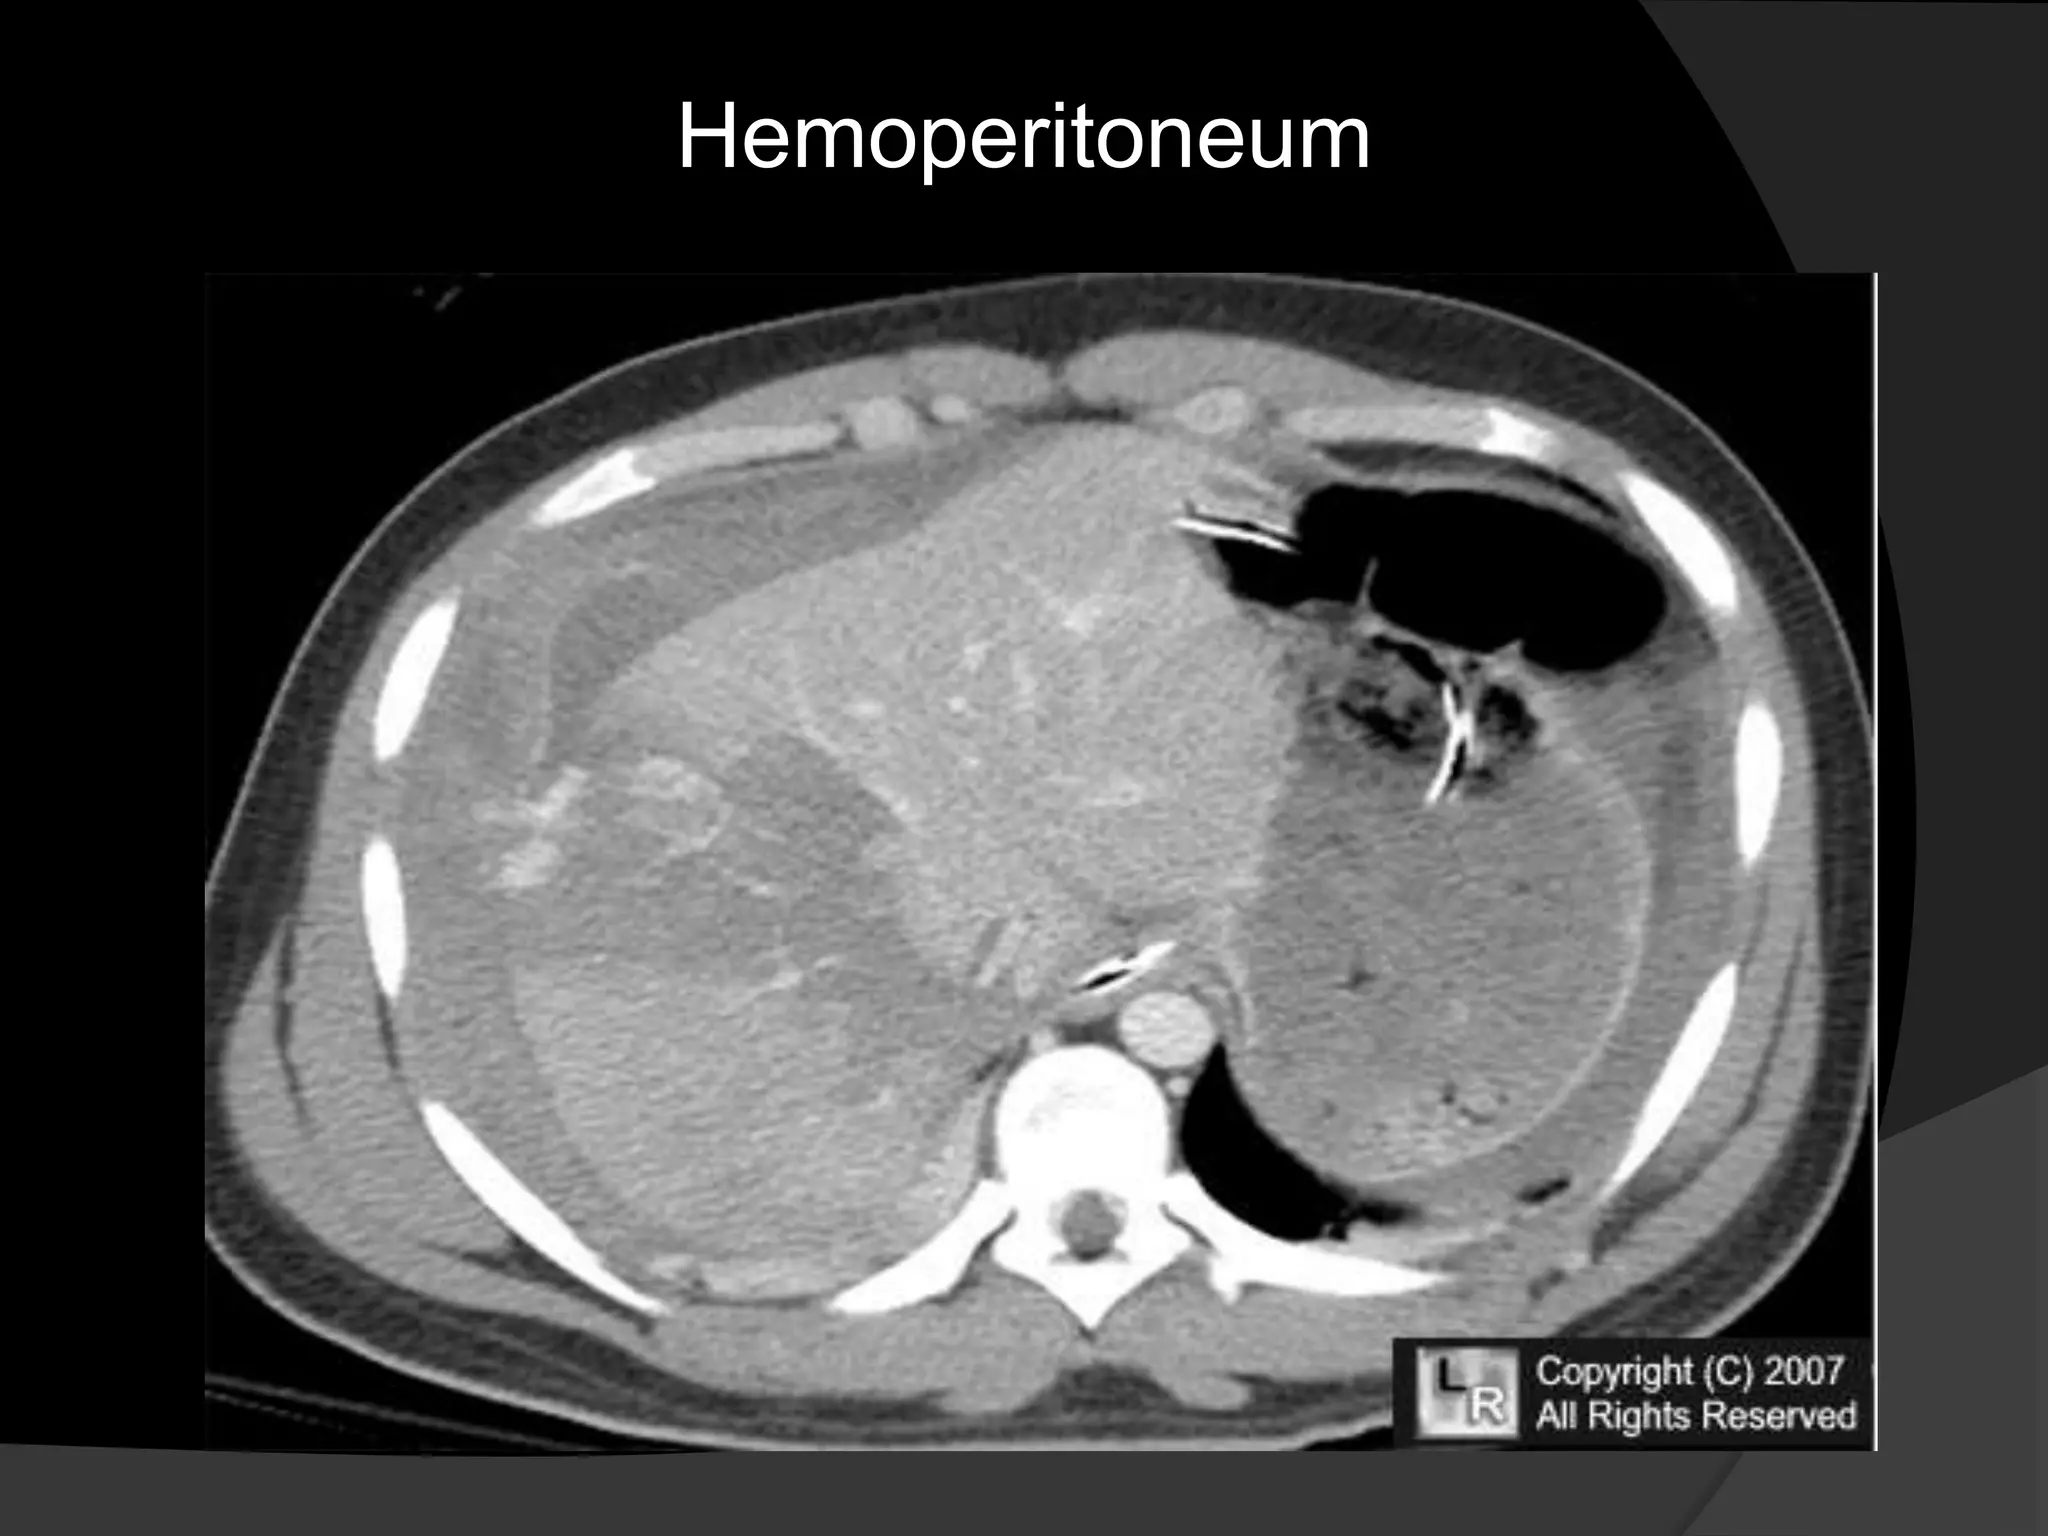

Hemoperitoneum